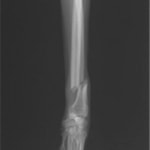

症例3:キルシュナーワイヤーのピンニングによる整復

ペルシャ猫 11ヶ月齢 雄

他院にて左大腿骨遠位の成長板骨折(salter-harrisⅠ型)が認められており、治療相談を目的として来院。当院にて、キルシュナーワイヤーを用いたピンニングにより骨折部位の整復を行いました。術後の経過は良好で、現在も経過観察中です。

術前レントゲン

術後レントゲン